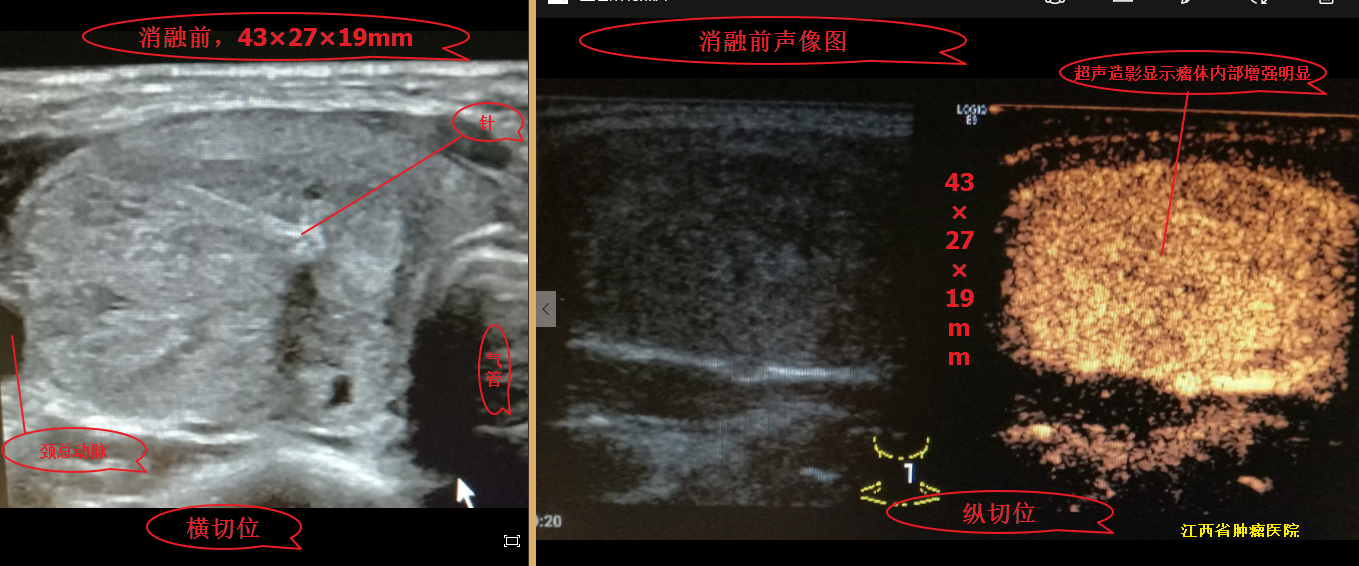

甲状腺结节微波消融术后,随访效果图! - 好大夫